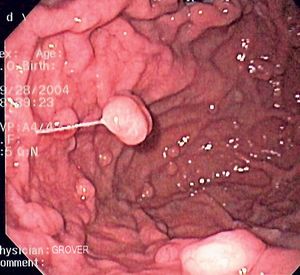

위선 폴립(polyp (medicine))의 내시경 사진